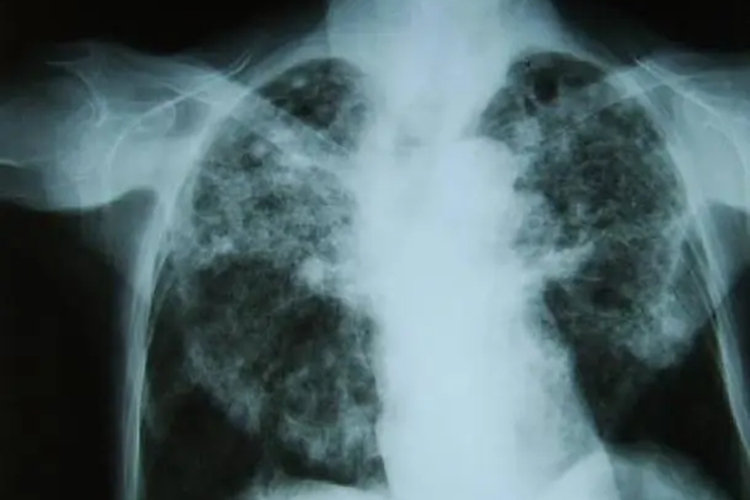

尘肺病X线的肺部主要表现为肺结节阴影(直径一般在1-3mm)、网状阴影和大片融合阴影;其次为肺纹理改变、肺门改变和胸膜改变。